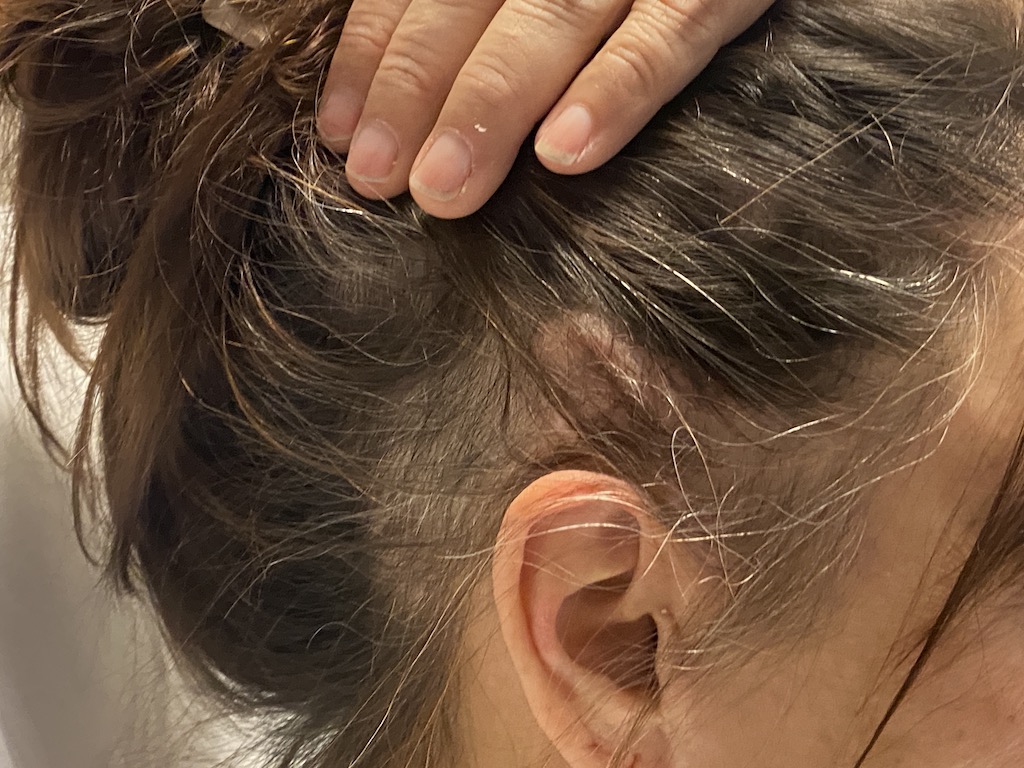

Patient 51

Desire for taller and rounder head shape.

Two stage custom skull implant augmentation technique.

Desire for taller and rounder head shape.

Two stage custom skull implant augmentation technique.